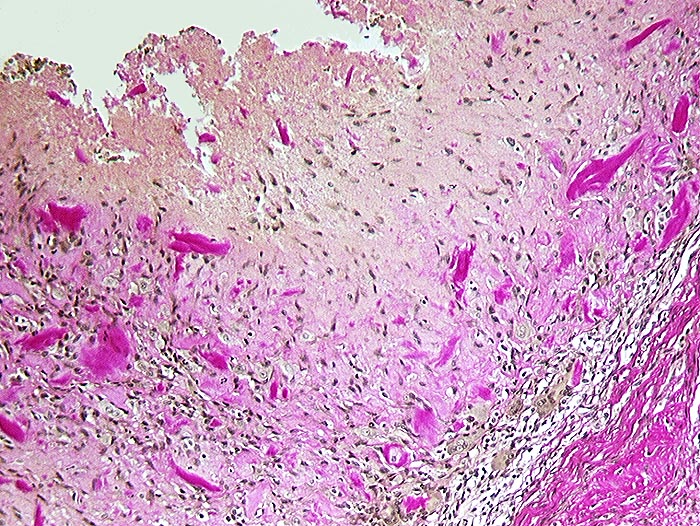

PathoPic – image database / PathoPic ID 1146 - Detritussynovialitis

Detritussynovialitis

Anstelle des Epithels finden sich avitale Knochensplitter eingebettet in Fibrin. Daran angrenzend Granulationsgewebe mit zahlreichen Fremdkörperriesenzellen.

Arthrose des Hüftgelenkes.